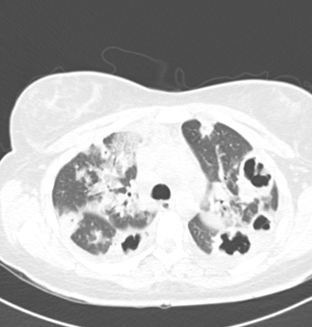

Fig 5.Chest x-ray; air-fluid-filled cavitary lesions bilaterally.

Fig 6.CT chest; cavitary lesions bilaterally.

On hospital day three, her chest x-ray and CT scan of the chest showed multiple cavitary lesions bilaterally consistent with septic emboli throughout both lung fields (Image 5, 6, click to enlarge). Subsequently blood cultures were positive for Fusobacterium necrophorum. A diagnosis was made of Lemierre syndrome and her antibiotic course was changed to ampicillin-sulbactam. The patient improved significantly and was discharged to home a week later.